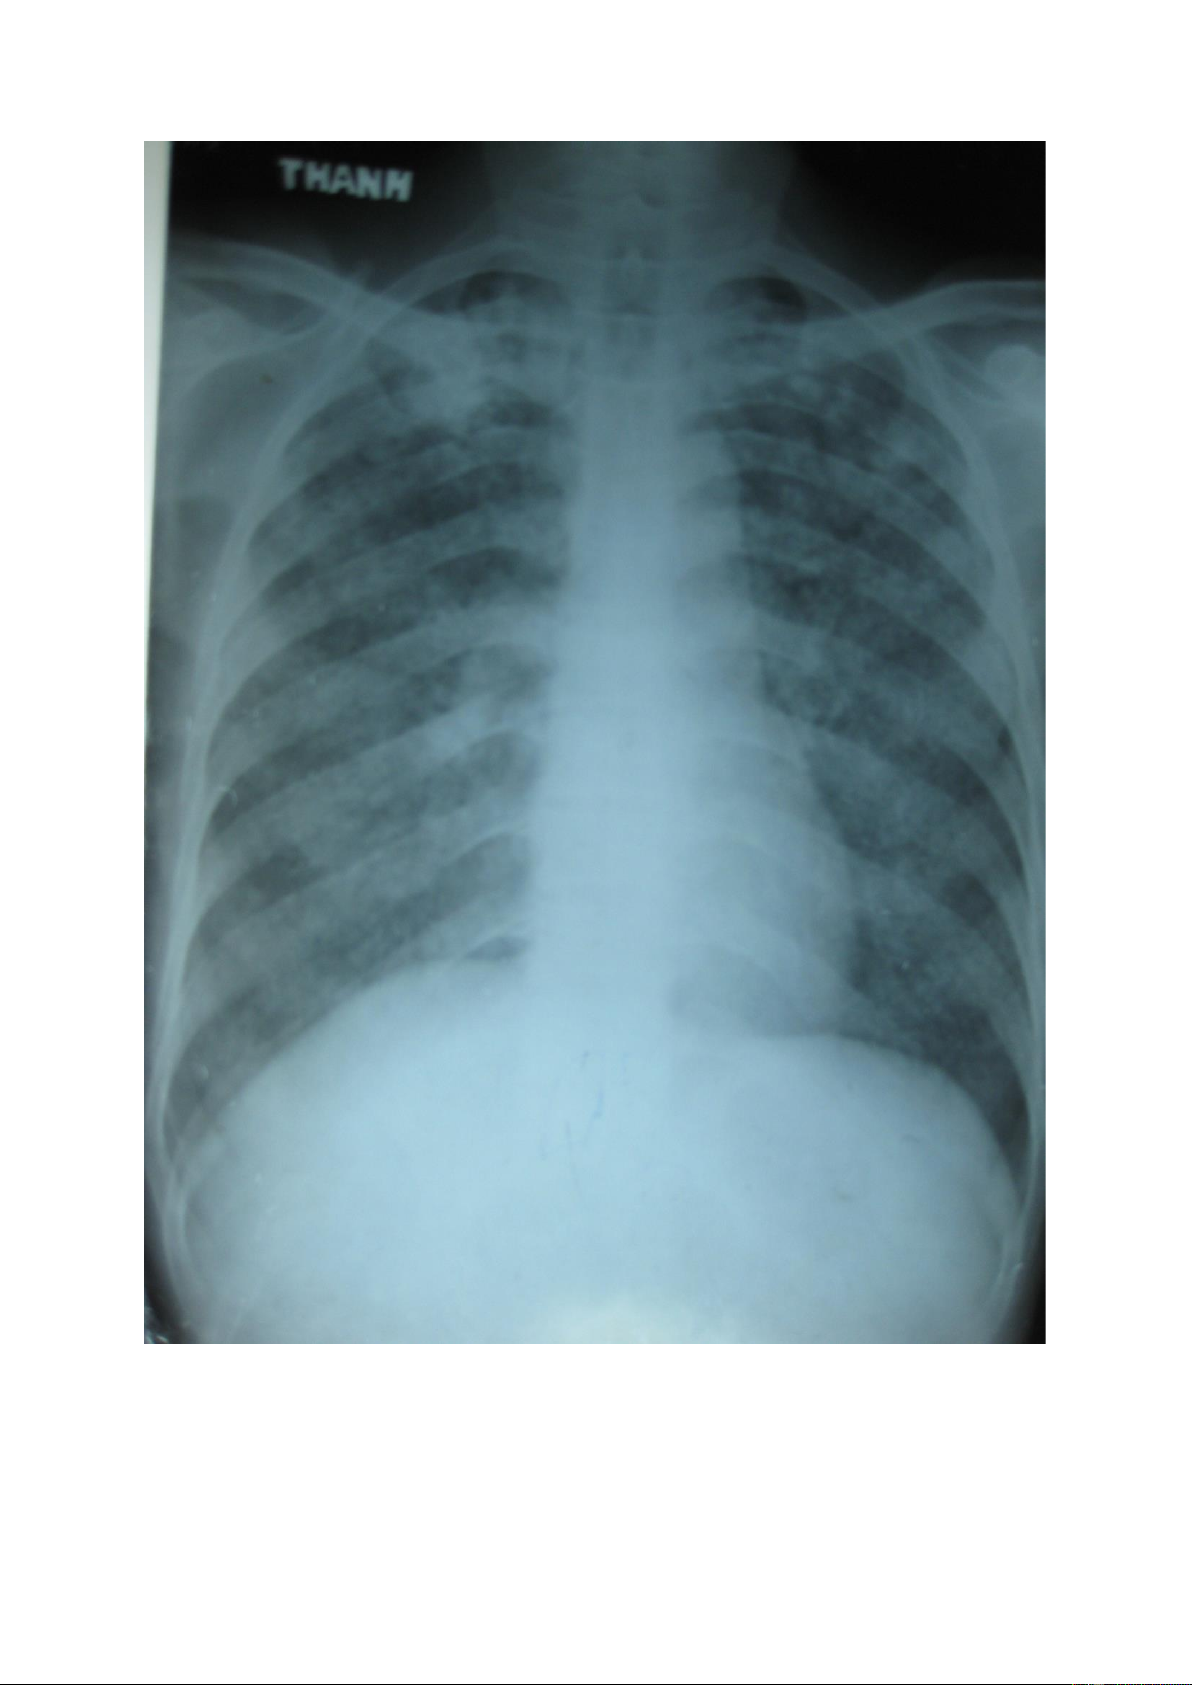

Đám mờ: là tổn thương có sự tập trung của các nốt mờ theo vùng tạo thành

hình ảnh vùng mờ không đồng đều, không rõ bờ của vùng tổn thương đó. lOMoAR cPSD| 22014077 1.5.